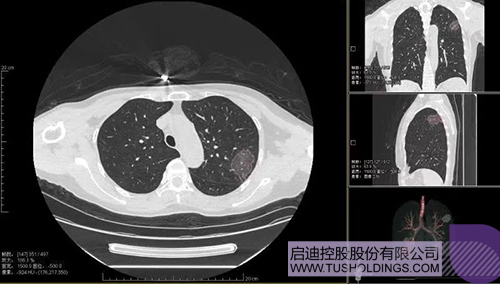

2020年2月11日,啟迪科服投資企業(yè)—神州德信推出新冠肺炎檢測(cè)及量化智能分析系統(tǒng),積極助力一線醫(yī)務(wù)人員科學(xué)精準(zhǔn)防疫。